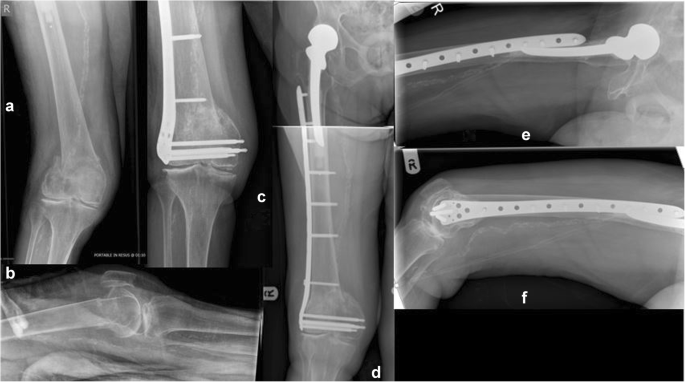

Fig. 4

figure 4

Type 33.C2 distal femoral fracture to a 67-year-old lady following a fall from standing height (a and b represent preoperative anteroposterior and lateral views of the right distal femur). Randomised to and fixed with a Polyaxial distal femoral plate and three free lag screws addressing the intra-articular extension of the fracture lines, (c, d, e). Uneventful fracture healing was evident to the radiological control at 6 months (f, g) and recovery of pre-injury levels of mobility, knee function, and overall health state recovery